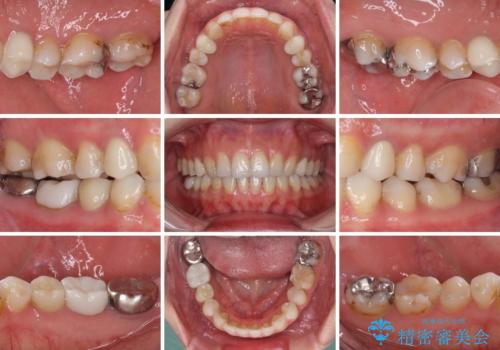

- 失活により変色した歯と不揃いな口元を気にして来院された患者様です。

口元をインビザラインにより歯列を整え、その後に失活している奥歯をオールセラミッククラウンにて補綴治療することとしました。

長時間のマウスピース装着と、患者様自身でのゴムかけに協力いただき、自然な口元に仕上げることができました。

気になっていた変色した歯もオールセラミッククラウンで本物の歯のようになり、患者様には大変満足していただきました。